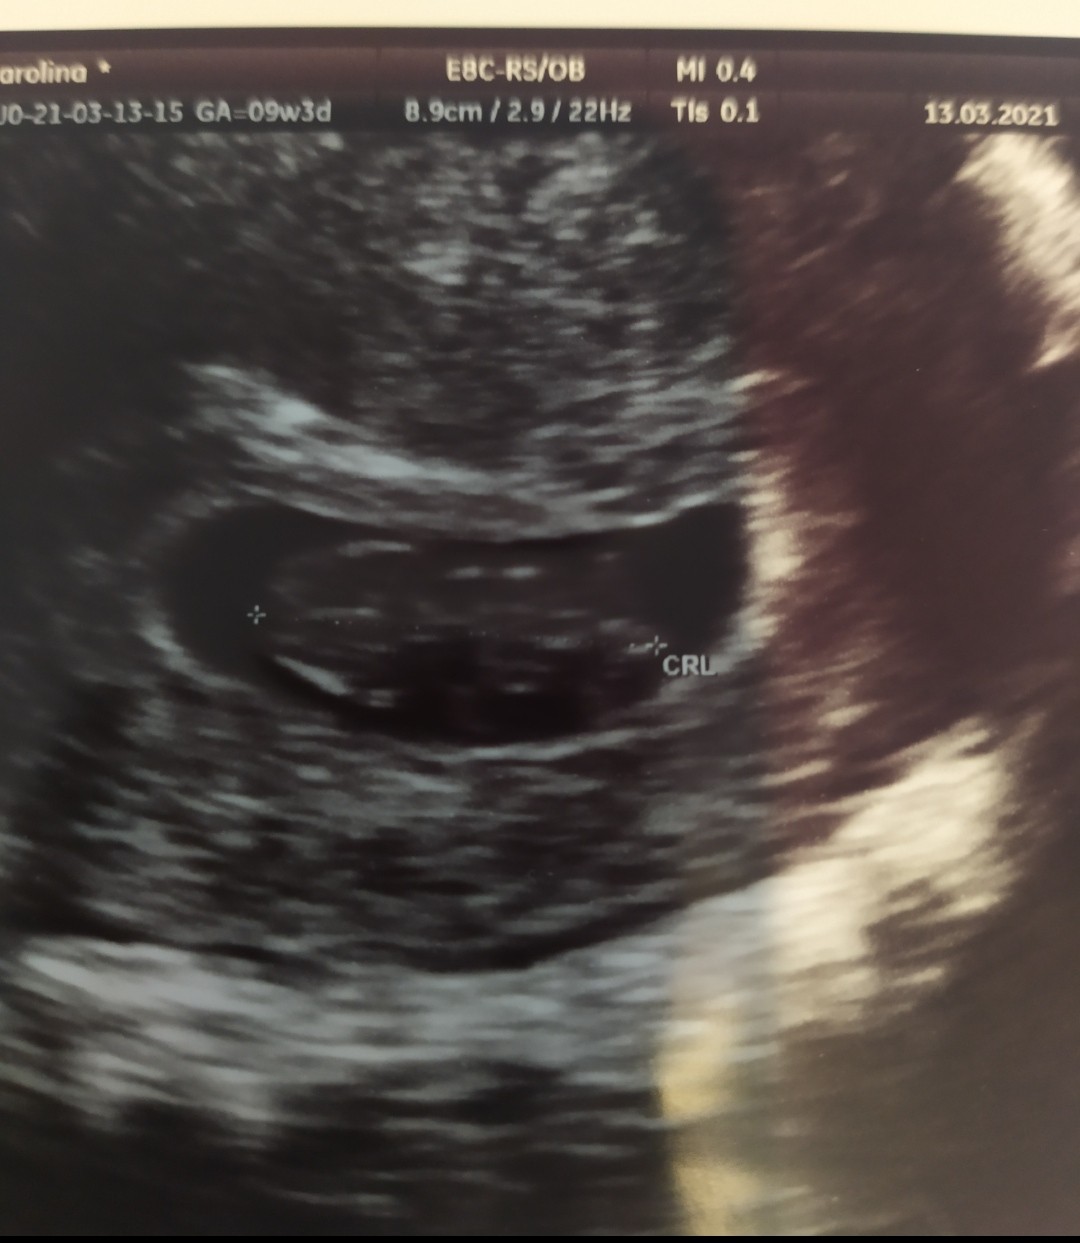

Melduje się po wczorajszej wizycie. Wszystko ok. Dalej tydzień opóźnienia pomiędzy OM a USG, ale z moimi długimi cyklami jakoś mnie to już nie martwi.

Bob nawet podobno się ruszał (ja nie widziałam). Ale lekarz zadowolony.

Pozwolił w końcu trochę pospacerować. Natomiast clexane, aspirynę i progesteron brac dalej do odwołania.